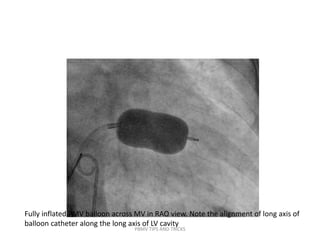

Fully inflated PMV balloon across MV in RAO view. Note the alignment of long axis of

balloon catheter along the long axis of LV cavity